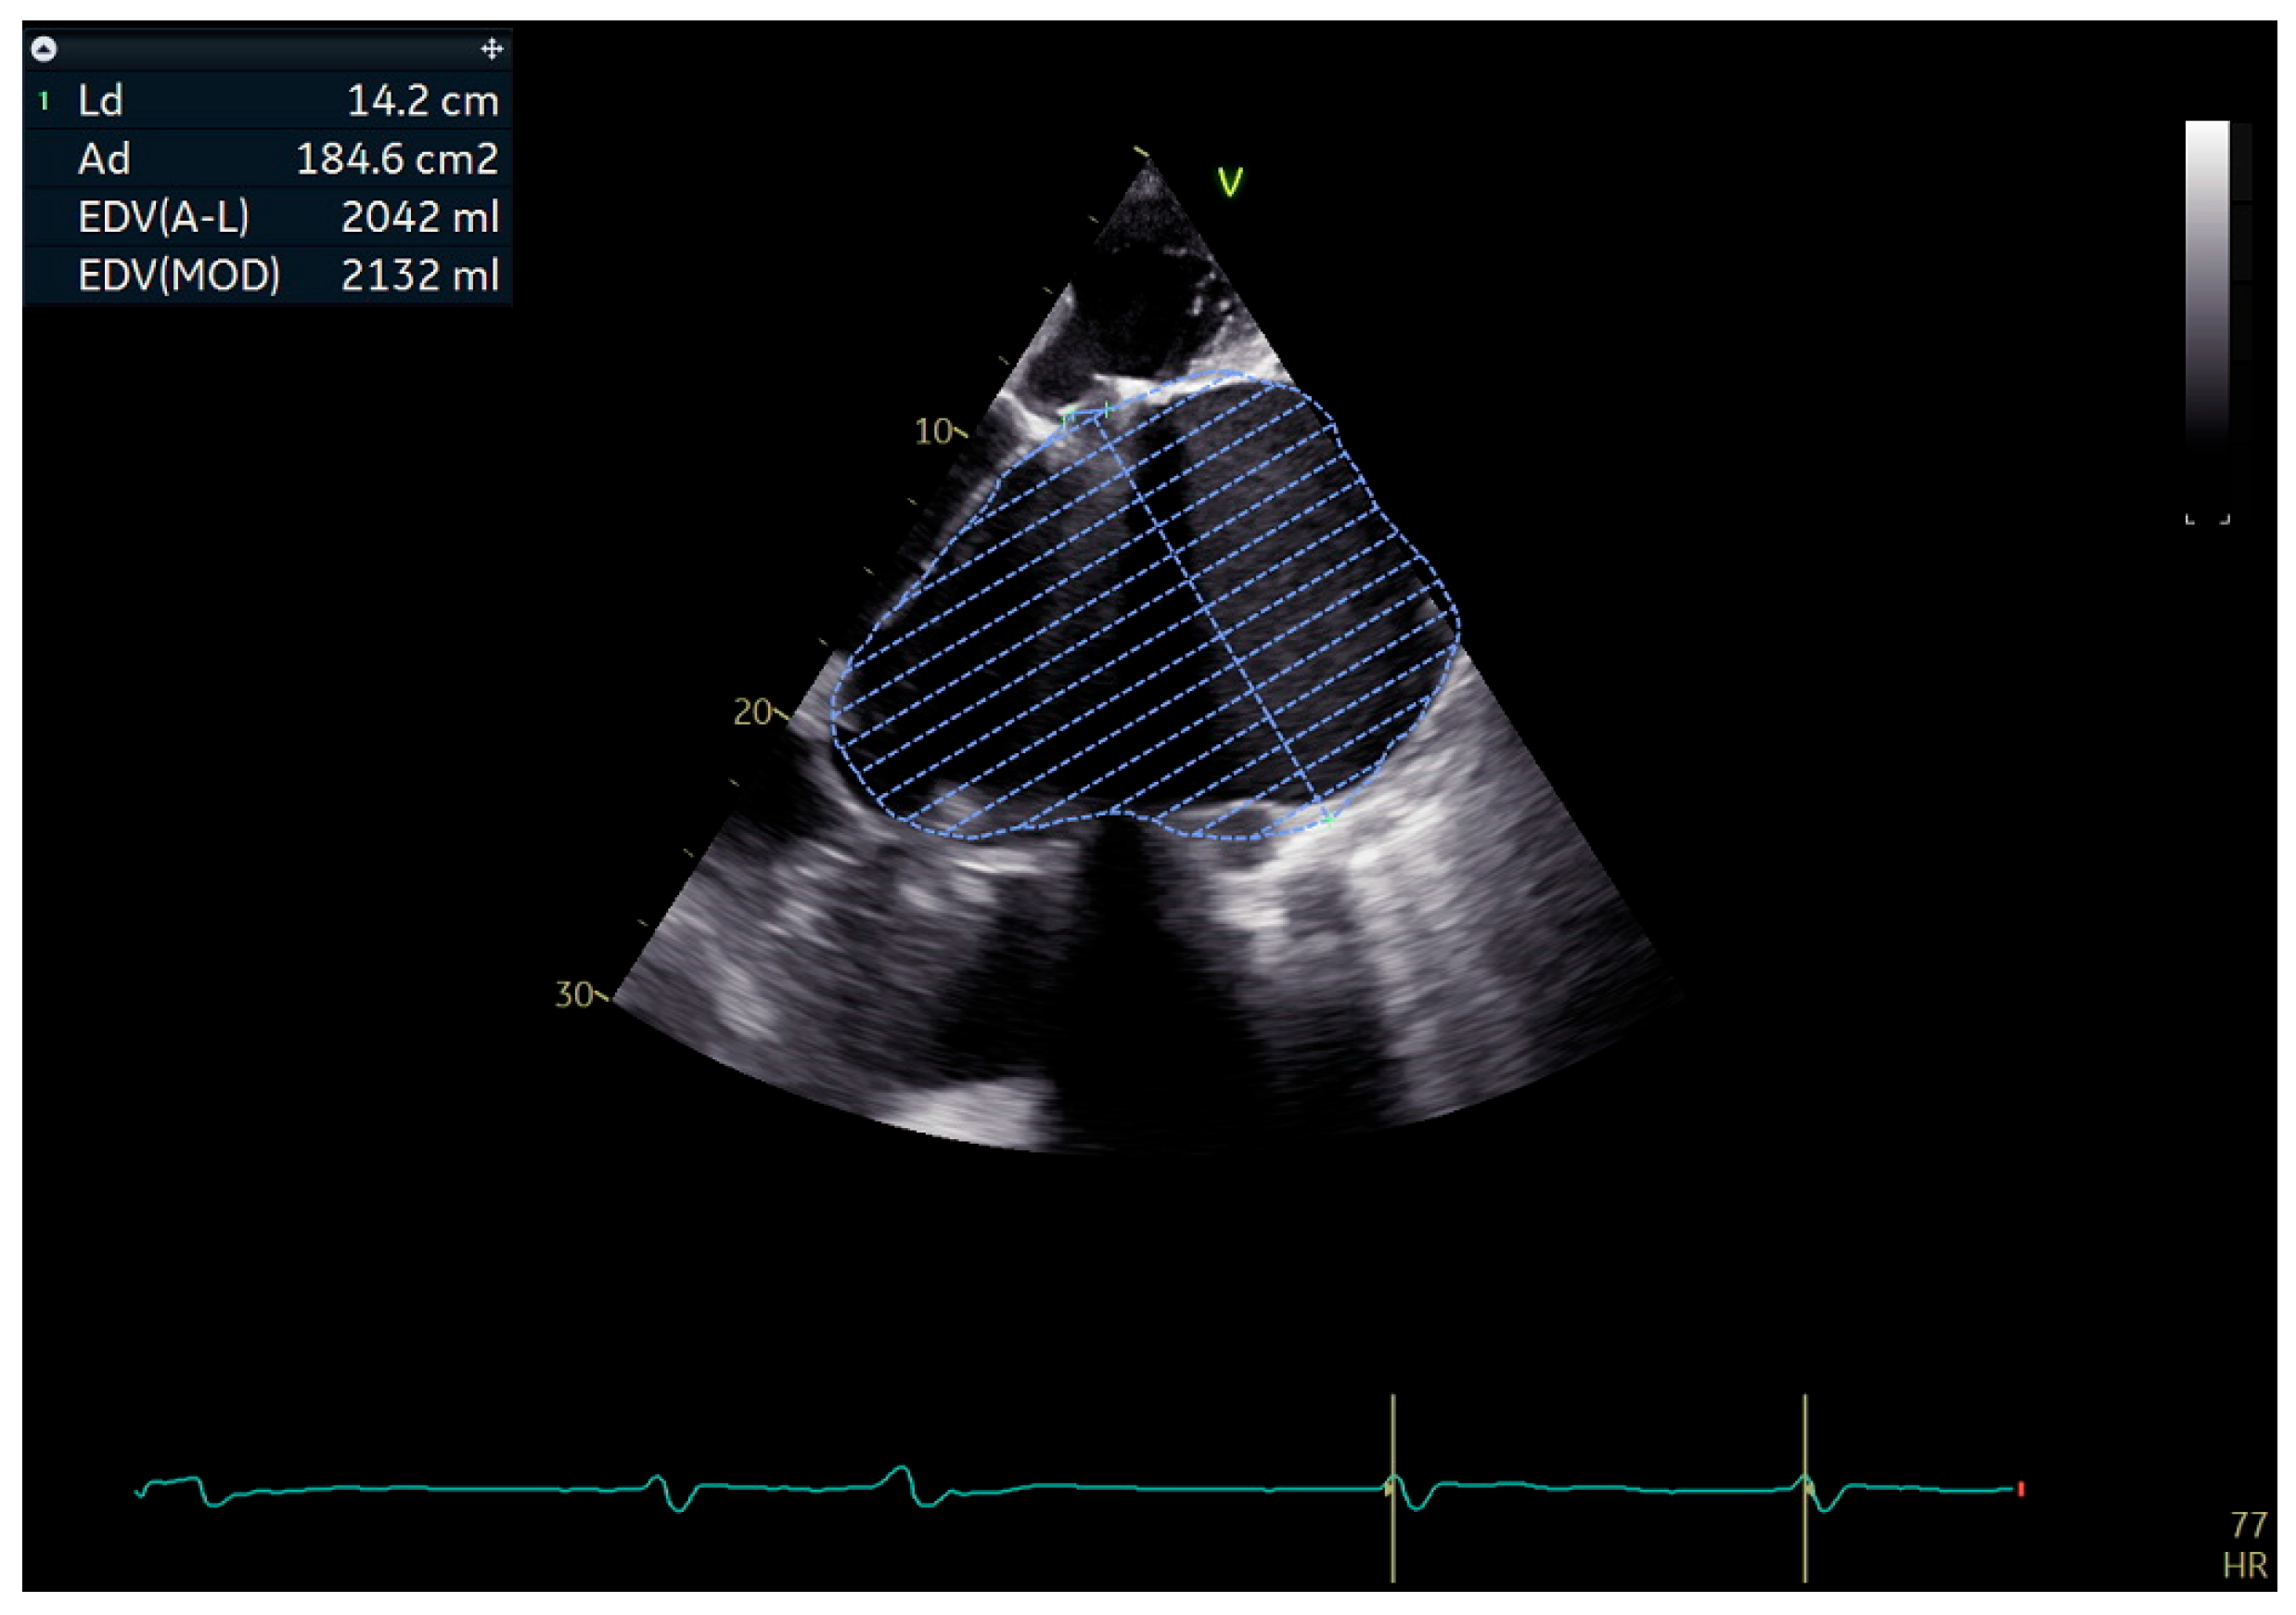

4. Case Presentation